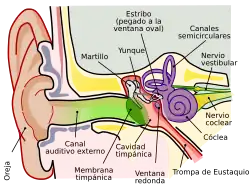

Estos tumores suelen aparecer en la entrada del nervio en el conducto auditivo interno, que es un canal óseo del peñasco del hueso temporal, que comunica el laberinto con la fosa craneal posterior, y que es atravesado por cuatro nervios: el nervio facial y el nervio coclear en el plano anterior, y los vestibulares superior e inferior en el plano posterior. Al iniciarse en la parte del nervio que está ya dentro del conducto óseo (intracanalicular), el crecimiento del tumor produce precozmente una compresión de las fibras del nervio coclear, que pueden llevar a la disminución o pérdida de audición y a ciertos trastornos del equilibrio (aunque estos se suelen ir compensando con las señales del otro lado).

Cuando ya tiene crecimiento intracraneal el tumor irá comprimiendo y afectando, en diversa medida hasta llegar a lesionar, al mismo nervio estatoacústico, al nervio facial, (que viaja paralelo a dicho nervio estatoacústico y cuya función es llevar los impulsos nerviosos necesarios para el movimiento de los músculos de la cara, incluidos los que cierran el ojo y mueven los labios), al nervio trigémino (que conduce la sensibilidad de la piel de la cara y de la córnea del ojo del mismo lado) y cuando alcanza mayor volumen puede llegar a comprimir el tronco cerebral, el cerebelo y el resto de nervios craneales.

Esta compresión sucesivamente irá afectando funciones como son: la audición, el movimiento de la cara, la sensibilidad de la cara, la deglución, el equilibrio, la precisión de los movimientos, el tono de voz, y pueden llegar a aparecer temblor, dolores de cabeza, hidrocefalia e hipertensión intracraneal, con grave afectación de las funciones vitales.